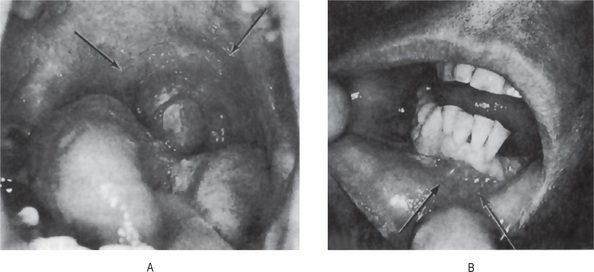

Figure 19-18 Hereditary benign intraepithelial dyskeratosis.

The white, macerated appearance of the lesions on the buccal mucosa is seen in (A). The peculiar ‘dyskeratotic’ cells are shown in (B) Courtesy of Dr Carl J Witkop.

The oral lesions of hereditary benign intraepithelial dyskeratosis appear generally as white, spongy, macerated lesions of the buccal mucosa, with or without folds (Fig. 19-18A). They are also described on the floor of the mouth, ventral and lateral surfaces of the tongue, the gingiva and palate. These lesions vary from delicate, opalescent white membranous areas to a rough, shaggy mucosa. Lesions frequently involve the corners of the mouth and appear as soft plaques with pinpoint elevation when the mucosa is stretched.

Patients with this disease also manifest lesions of the eye characterized by superficial, foamy, gelatinous white plaques overlying the cornea, sometimes producing temporary blindness. In addition, the conjunctivae are usually intensely congested. Interestingly, these eye lesions in some cases show a seasonal variation, tending to appear or increase in severity in the spring and disappear, sometimes by spontaneous shedding of the pseudomembrane, in late summer or fall.

Sections of the buccal mucosa exhibit thickening of the epithelium with pronounced hydropic degeneration. In addition, numerous round, waxy-appearing eosinophilic cells resembling minute epithelial pearls are evident, the ‘dyskeratotic’ cells (Fig. 19-18B). An excellent detailed description of the microscopic features of this disease has been provided by Witkop. Sadeghi and Witkop also have described ultrastructural differences between the mature dyskeratotic cells in this disease and in other dyskeratotic conditions of the mucous membranes.